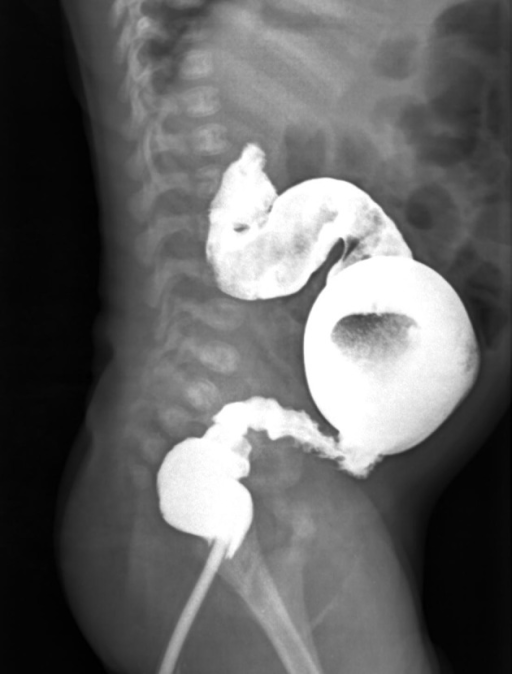

Diagnostic accuracy of radiologic scoring system for evaluation of suspicious hirschsprung disease in children. Alehossein M, Roohi A, Pourgholami M, Mollaeian M, Salamati P - Iranian journal of radiology : a quarterly journal published by the Iranian Radiological Society (2015)